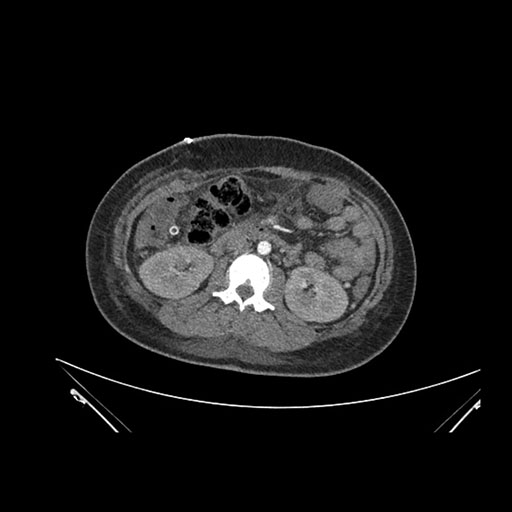

Imaging Analysis

Look through the patient's CT scan to identify any areas of concern for the necessary procedure.

Axial Arterial